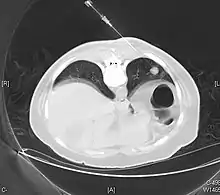

Typical pulmonary carcinoid tumour is a subtype of pulmonary carcinoid tumour. It is an uncommon low-grade malignant lung mass that is most often in the central airways of the lung.[1]

Lung carcinoids typically present with a cough or hemoptysis.[2] Findings may closely mimic malignant tumours of the lung, i.e. lung cancer.